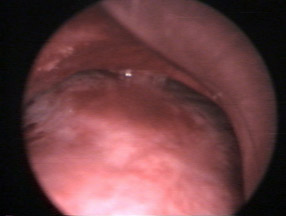

Elle permet la réalisation des

vidéo-bronchoscopies souples classiques sous anesthésie locale ou sédation par

protoxyde d’azote, la détection précoce des anomalies bronchiques par

techniques d’auto-fluorescence mais également toutes les techniques de ponction